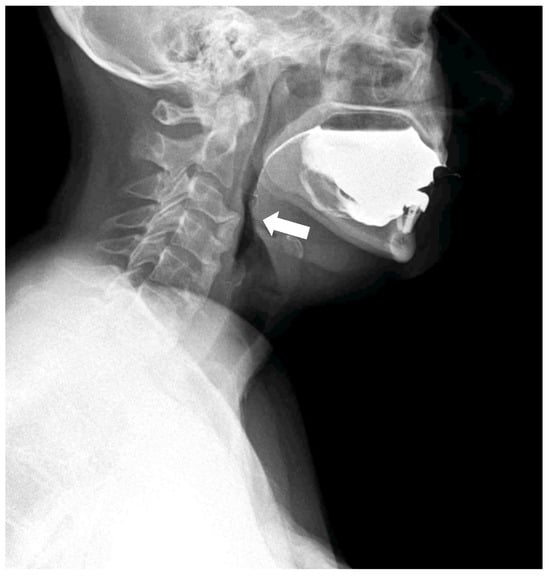

Figure 3. The patient adopted a compensatory swallowing position with neck and chest flexion forward to reduce pharyngeal narrowing and facilitate bolus passage. The pharyngeal lumen is narrowed by the anterior cervical osteophytes. Compared with traditional videofluoroscopic examinations, DDR offers a wider field of view, quantitative motion analysis, and significantly reduced radiation exposure [,,]. In the context of swallowing disorders, DDR allows simultaneous evaluation of bolus transit and the impact of mechanical obstructions, while also detecting compensatory strategies adopted by the patient. Moreover, DDR technology is available on portable equipment; this allows the clinicians to conduct a swallowing study directly at the patients’ bed, which is particularly important when dealing with frail patients affected by dysphagia and silent aspiration. The whole dynamic acquisition captured at 15 frames/s is presented in Supplementary Material S1.

Figure 4. The compensatory position with the anterior flexion of the neck and chest is effective in slightly reducing the compressive effect of the osteophyte and ligament calcification to enable the contrast bolus passage (white arrow).

The following are available online at https://www.mdpi.com/article/10.3390/diagnostics15233020/s1, Video S1: Dynamic swallowing study. The patient spontaneously adopted a compensatory swallowing strategy with neck flexion, which partially reduced pharyngeal narrowing and facilitated bolus passage. The pharyngeal lumen is narrowed by the anterior cervical osteophytes.